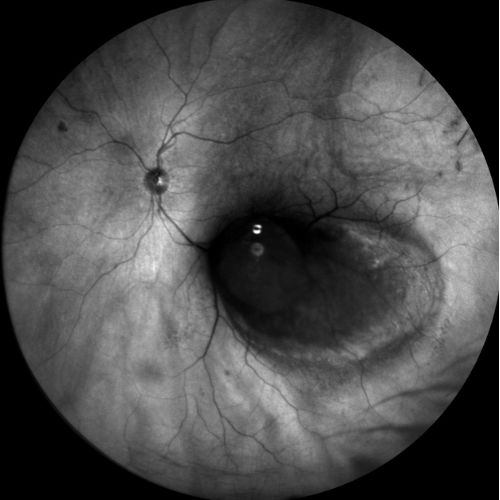

Autofluorescenza

Infrarosso

Fluorangiografia